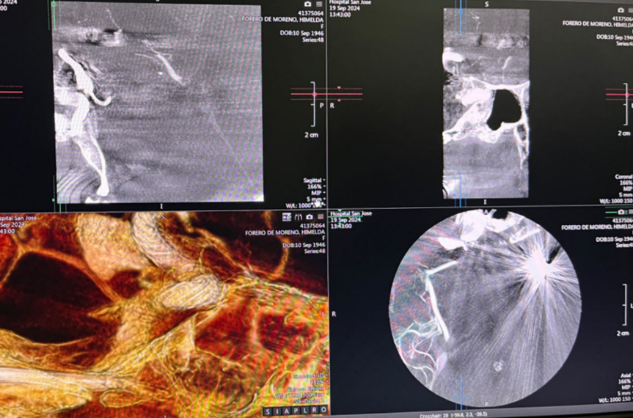

Immediate post-procedure angiography

Post-deployment angiography confirmed clear stent visibility, excellent wall apposition, unobstructed distal vessels and branches, and obvious contrast stagnation within the aneurysm sac—showing a distinct “crescent sign.” The delivery system was then successfully retrieved.

Clear visualization of the stent

Postoperative Outcome

Multiview angiography after the procedure showed optimal wall adherence of the Nuva® stent, with no signs of intracranial hemorrhage or ischemia. The operation concluded successfully.